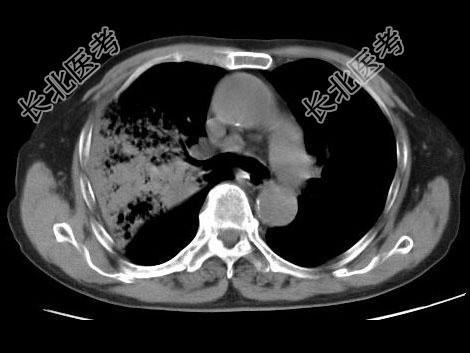

- 单项选择题男,23岁, 高热,咳铁锈色痰, 胸部CT扫描如图,最可能的诊断为 ( )

A、右上肺干酪性肺炎

B、右上肺金葡菌肺炎

C、右上肺大叶性肺炎

D、右上肺中央型肺癌

E、右上肺肺结核